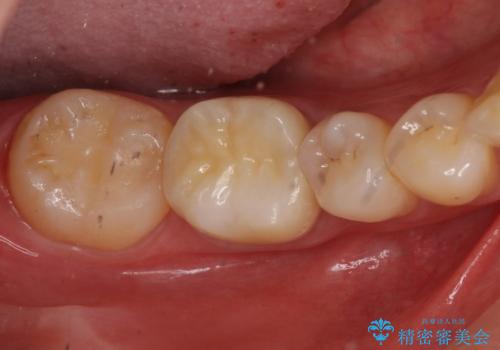

銀歯を白くしたい セラミッククラウンでのやり替え